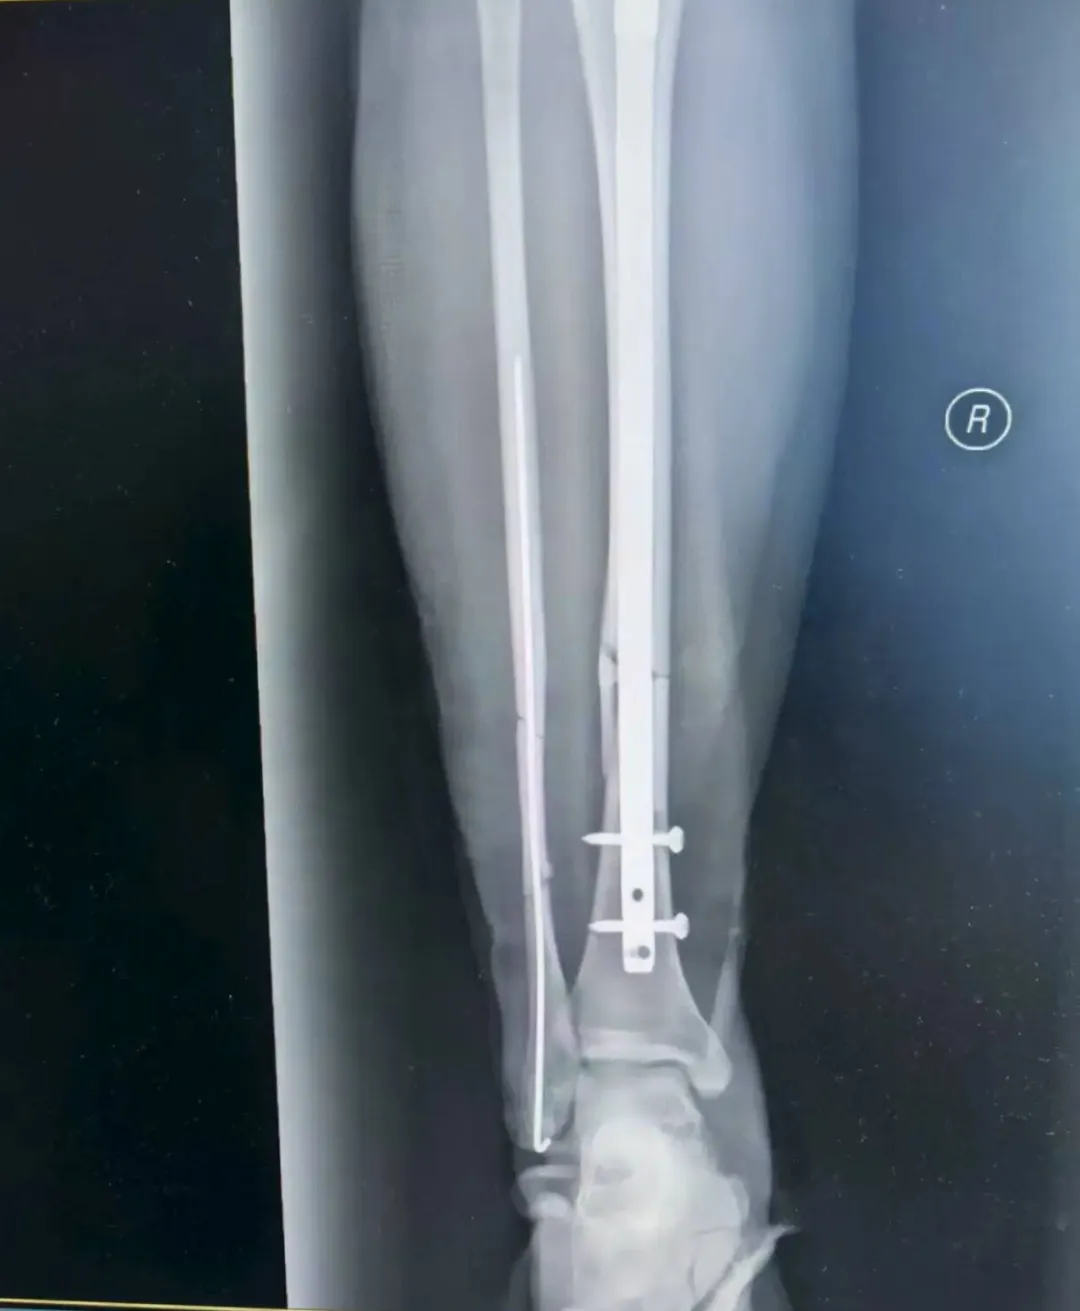

考虑到张女士是外地游客,不仅希望骨折能精准复位,还盼着创伤小、恢复快,不耽误后续返程与康复。董伟副主任医师结合影像学资料,综合考虑张女士的身体状况与个人需求,最终确定采用“胫腓骨骨折闭合复位+胫骨髓内钉内固定术+腓骨髓内针内固定术”,全程无需做大切口,通过微创方式实现骨折端精准对位,既能最大程度保护肿胀的软组织,又能显著提升术后恢复速度。

精细手术操作

手术由董伟、孙毅珲共同完成,术中借助C臂机实时透视引导,小心翼翼地通过闭合复位技术调整骨折端位置,确保达到解剖复位标准;随后精准植入胫骨髓内钉与腓骨髓内针,完成固定。整个手术过程出血少,术后仅留下几个微小创口,最大程度减少了张女士的痛苦。

如今术后已经一周,张女士恢复情况远超预期:微创留下的针眼愈合良好,没有出现红肿、渗液等异常情况;主管医生孙毅珲每日都会到病房查看她的恢复情况,指导她完成床上肌肉训练——从踝泵运动到股四头肌收缩,张女士每个动作都做得认真,“孙医生每天都耐心教我怎么练,现在小腿不怎么肿了,也不怎么疼,能明显感觉到腿上的劲儿在慢慢回来”。